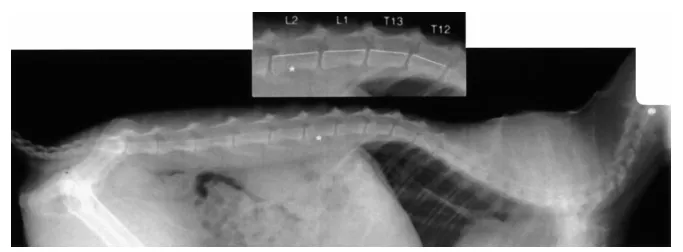

通过对猫的X光分析和角度测量,研究人员发现猫的脊柱在扭转方面(绕着脊柱纵轴的旋转运动)有着极高的灵活性,尤其是胸椎中段(T4 至 T11)的扭转范围非常广。实验中测量了猫脊柱在最大扭转时的角度变化,发现扭转角度接近180度。

而且脊柱椎骨之间的间隙较大,并且猫的椎间盘非常柔软,有助于脊柱的极大可动性。这种结构允许猫的脊柱在前后弯曲时产生更大的弧度,提供了类似“弹簧”的效果,使得它们能够快速扭转或跳跃,也能够钻过更小的空间。